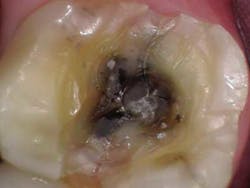

At the crown appointment, the amalgam filling and compromised mesial and distal marginal ridges were removed. The fracture line was indeed detected and noted to extend across the floor in a mesial/distal fashion.Fig. 3

The entire area was cleaned out, a build-up was placed, and the tooth was prepped for a full zirconia crown. At the end of the appointment, the patient was shown the picture of the fracture line and was informed that even though the tooth did not present in an irreversible nature, it still could need a root canal in the unforeseen future.